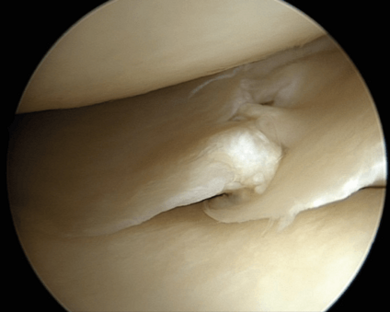

Die Operation erfolgt arthroskopisch („Schlüssellochchirurgie“). Je nach Art des Risses, Lokalisation sowie Beschaffenheit des Meniskus wird der Riss genäht oder der instabile Anteil des Meniskus entfernt.